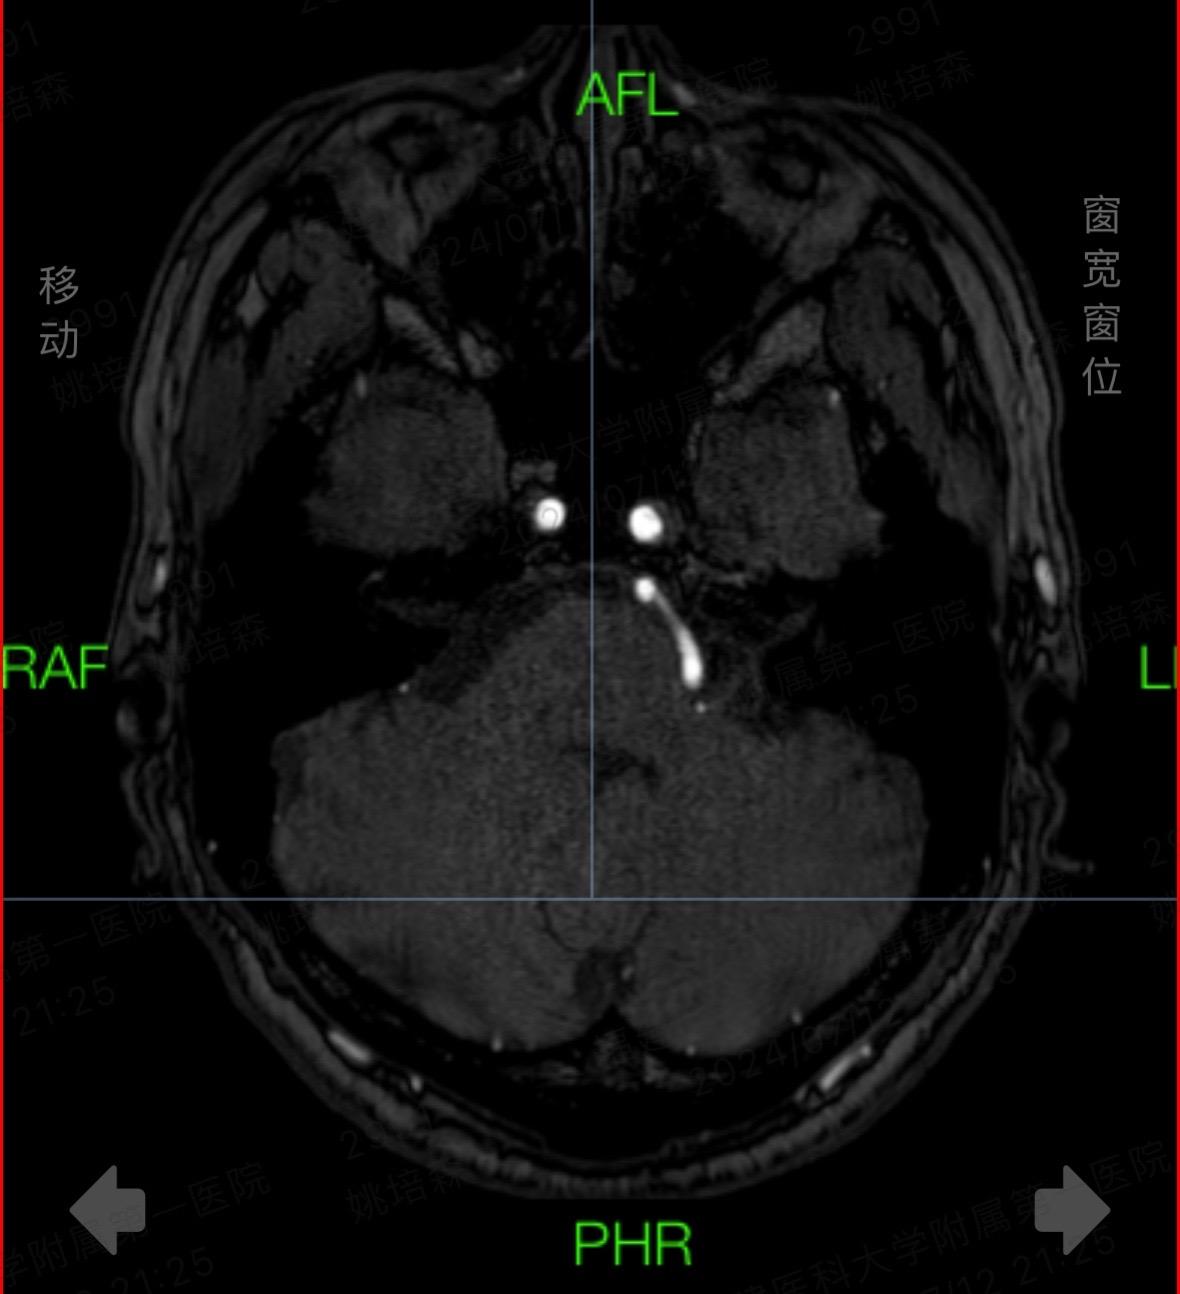

抗“帕”治疗,我们一直在路上!分享一位特殊帕金森患者,居然在右侧STN...